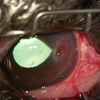

光を当てると、縫合した部位と傷があった部位には瘢痕が残っていますが、

もともとあった症状はなくなり、今では点眼もいらなくなっています。